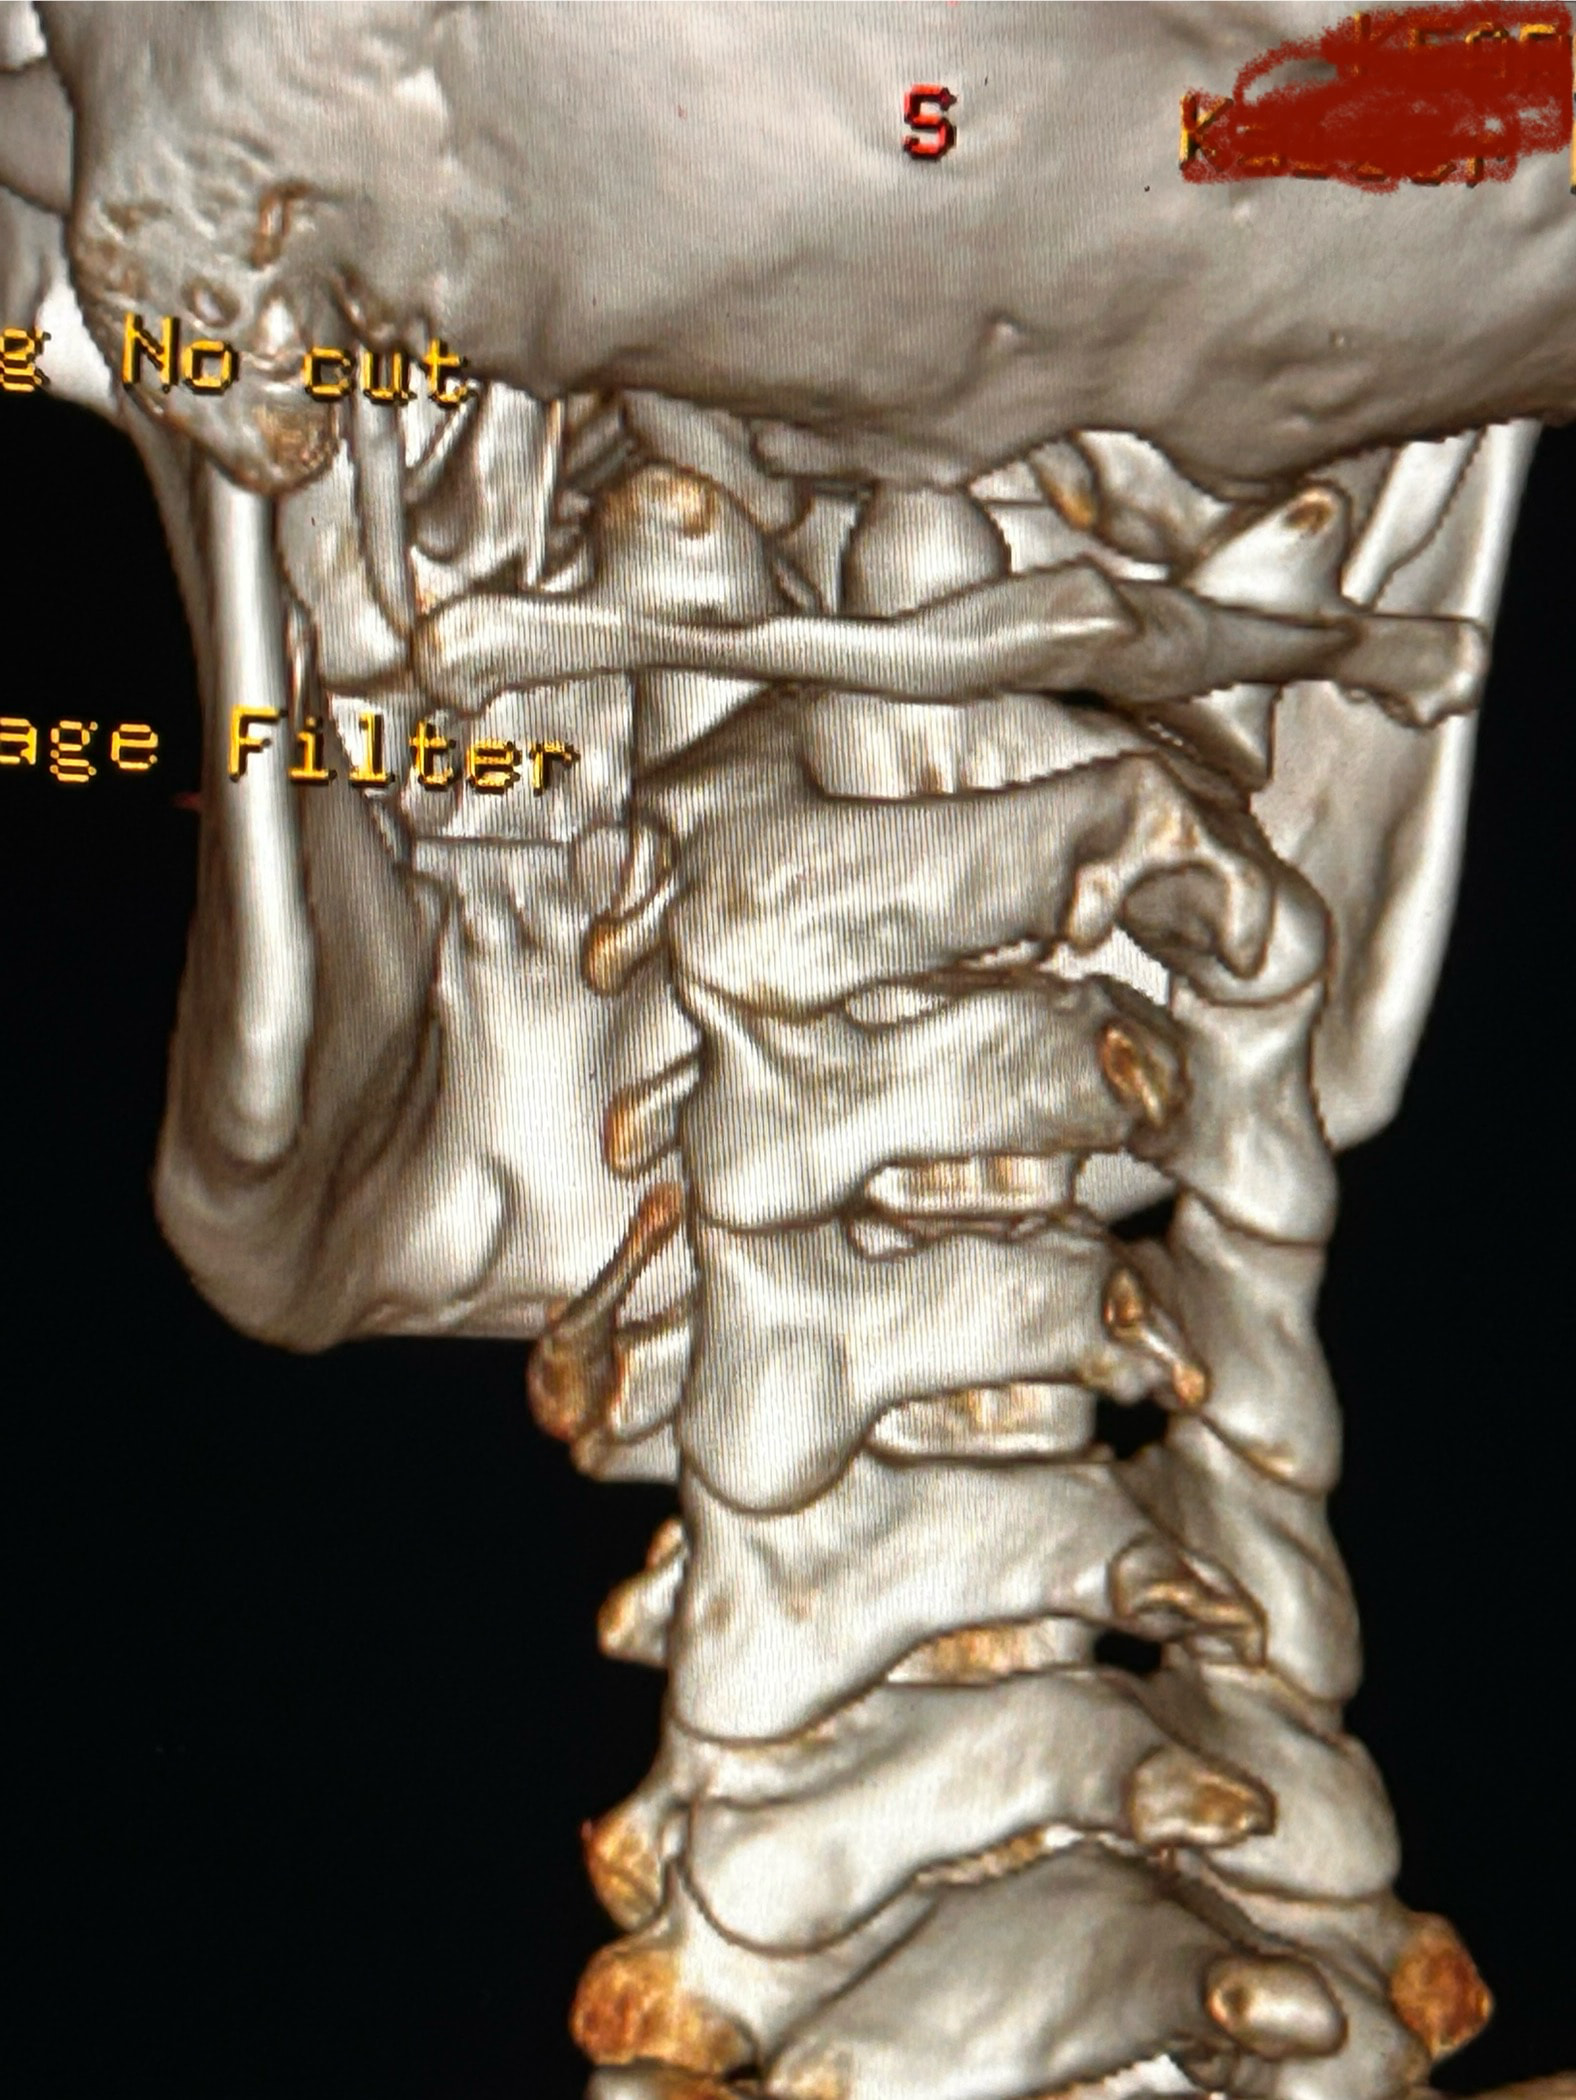

Here are some images of my 3-d ct, thanks for taking an interest it means a lot!

Oh and I almost forgot these were taken before I had my right styloidectomy

In this image of your left styloid, it appears from the angle of the picture that your left styloid is extremely close to the left transverse process of C1 (green circled area). If that’s truly the case, your left IJV is likely being squashed between the two & that means your vagus nerve is most likely being squashed at that point, too. Some of your symptoms could be vagal related. Also due to the angle of the image, it appears the greater horn of your hyoid could be very close to your spine which can cause internal/external carotid artery compression but can also cause symptoms that point to hyoid bone syndrome as you’ve suggested. Unfortunately, it doesn’t appear the CT scan was done w/ contrast as none of your veins or arteries appear in the images you posted & contrast is necessary to see those.

I’ll just add in as well that in your first image, the hyoid bone processes look pretty thick, more than you’d expect, so could well be part of your issues, but I do agree with @Isaiah_40_31 that your left styloid is very close to the C1 process, the right side looks a little longer than average… Also looking at the 1st & last images (I’m sorry, | can’t label them for you), there’s calcification below your hyoid which I’m presuming is the thyroid cartilage, it lookd pretty chunky compared to most people’s, so this could possibly be causing some issues too?

Thank you for the additional images. After reading @Jules observations, I went back over the first 4 images you sent & realized I’d miss some significant things. I’ve annotated more images for you below:

This one shows your right hyoid greater horn from behind.

I totally missed that I could see your whole hyoid bone from the front in this image. Jules is right, your greater horns are very thick from top to bottom. You can also see that your left greater horn is pretty straight, but the right one has an upward curve to it. I’m not sure what the calcification is below your hyoid but it’s most likely thyroid since the thyroid sits just below the hyoid in the neck.

In this image, you can see the differences in the shapes of your hyoid’s greater horns. The right one is more curved but the left one is thicker in width medial to lateral. In this image from the front it looks like both greater horns may be contacting your cervical spine in certain head positions, but again, that may an illusion created by the angle of the image.

In the final two images you sent, the right greater horn is very close to your cervical spine so there’s a good chance it’s causing you some problems as well as possible carotid artery irritation or compression in different head positions. The image of the left one doesn’t show as much of the greater horn so I can’t tell how close to the spine it is. Can you back the left image out a bit so it looks more like the right one?